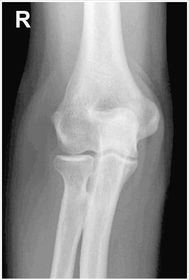

| AP Elbow | humerus is externally rotated because the epicondyles are not in profile |

| AP Elbow | ANATOMY: distal humerus - proximal forearm CRITERIA: slight superimposition of proximal radius/ulna humeral epicondyles in profile open joint space POSITIONING: CR perpendicular @ midelbow |